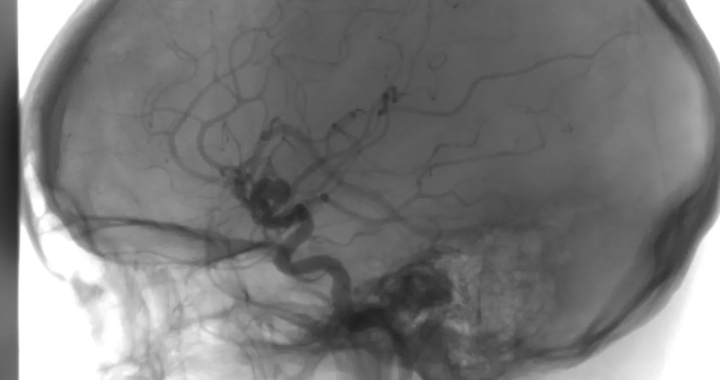

- Rzadka, niegenetyczna wada w  mózgu (poczwórna malformacja tętniczo-żylną z przetokowością),

- Zabieg DSA, WIM - listopad 2024

- Skierowanie WIM na operację embolizacji 4 naczyniaków tętniczo żylnych przetokowych - grudzień 2024

- Operacja embolizacji, WIM - bez powodzenia w związku z wysokim ryzykiem śmierci - marzec 2025